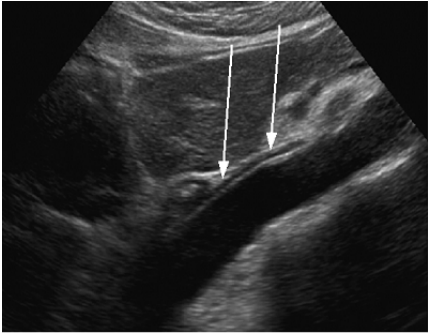

57. 附圖影像中箭號標示處是下列何者?

(A)頸部軟組織影像 (B)頸部移動假影(motion artifacts) (C)肩胛軟組織影像 (D)頸部組織反摺(aliasing)影像